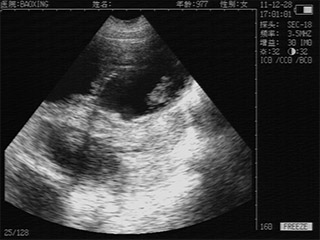

优质图像